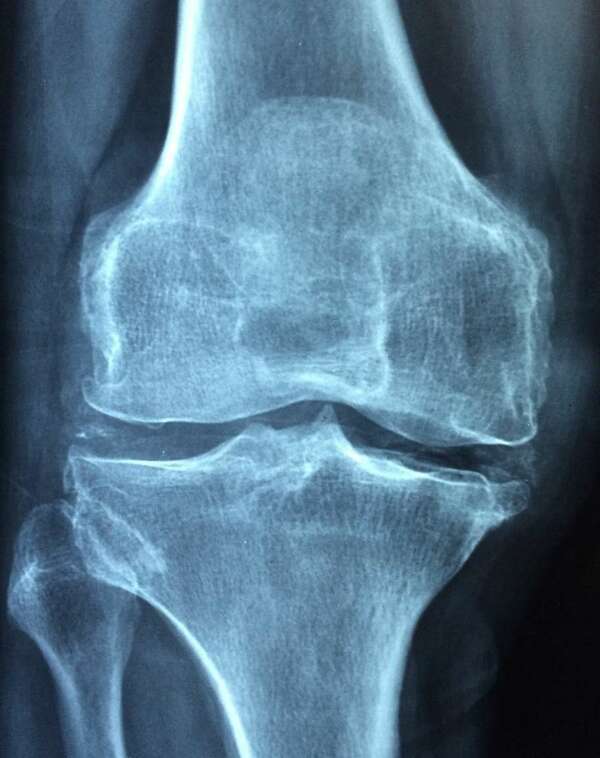

L’arthrose est une pathologie ostéo-articulaire chronique et dégénérative qui touche le cartilage mais également les éléments périphériques de l’articulation comme la membrane synoviale, l’os, la c...